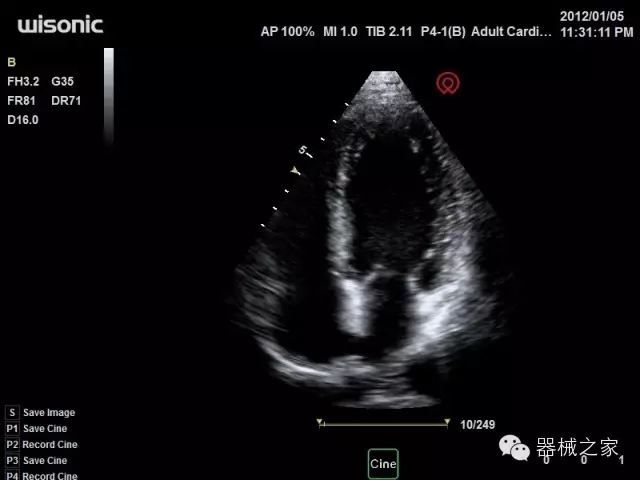

臨床圖片賞析

產(chǎn)品特點

·全球目前唯一一款配備主機(jī)雙探頭接口,整機(jī)重量(含電池)在5公斤以內(nèi)的便攜式彩超;

·獨有的HoloTM PW 實時3取樣門PW成像技術(shù),精確進(jìn)行血管診斷;